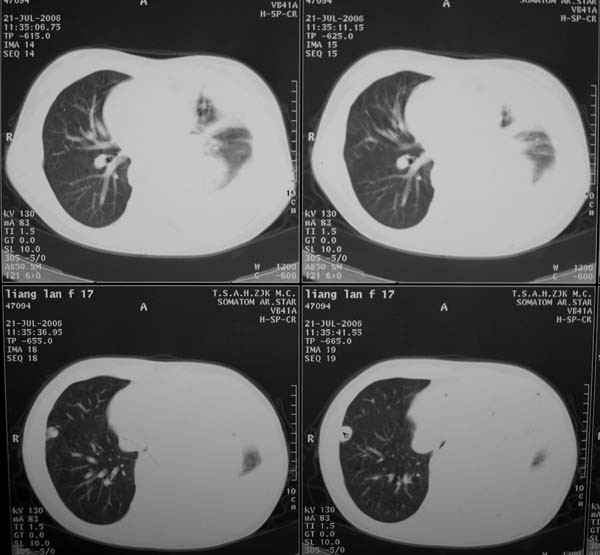

女性,17岁,一年前因股骨病变截肢,现胸憋。

股骨下段针状瘤骨垂直于骨皮质向外生长.并见软组织密度肿块影.骨髓腔密度增高.考虑股骨下段成骨肉瘤.胸膜及左肺转移瘤.

左肺巨大肿块,内散在斑点状高密度骨化影,右肺见多发结节灶,双侧胸膜局限性增厚。有骨肉瘤病史,支持骨肉瘤手术后转移。